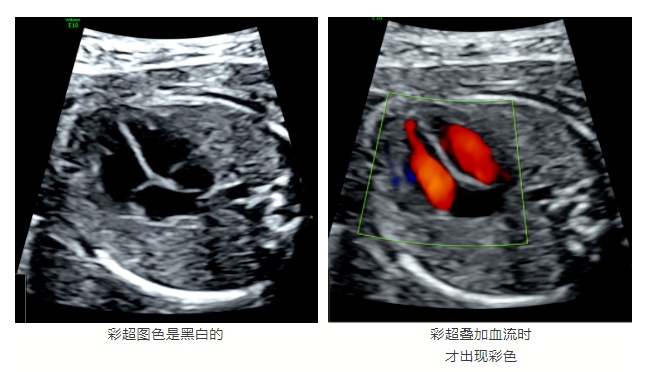

彩超的图像一定是彩色的

“这是很多患者都存在的误区。”超声检查是一种灰度超声,对人体组织通过不同黑白的成像密度来显示图像,让我们看得到,所以它是黑白的。彩超显示的是血流情况,而不是整个脏器像彩色电视机那样呈现五颜六色。